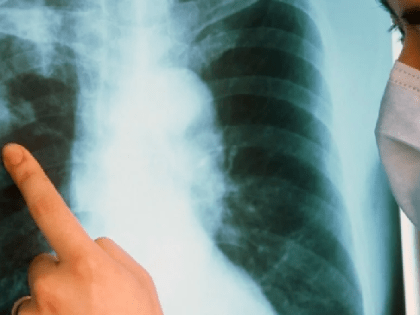

Неожиданный всплеск пневмоний произошёл в Ивановской области

Даже с учётом КТ рост – внушительный Фото: ok.ru/group/57309192454349 Всего 2 недели продержалась в Ивановской области обнадёжившая было тенденция на снижение числа пневмоний.